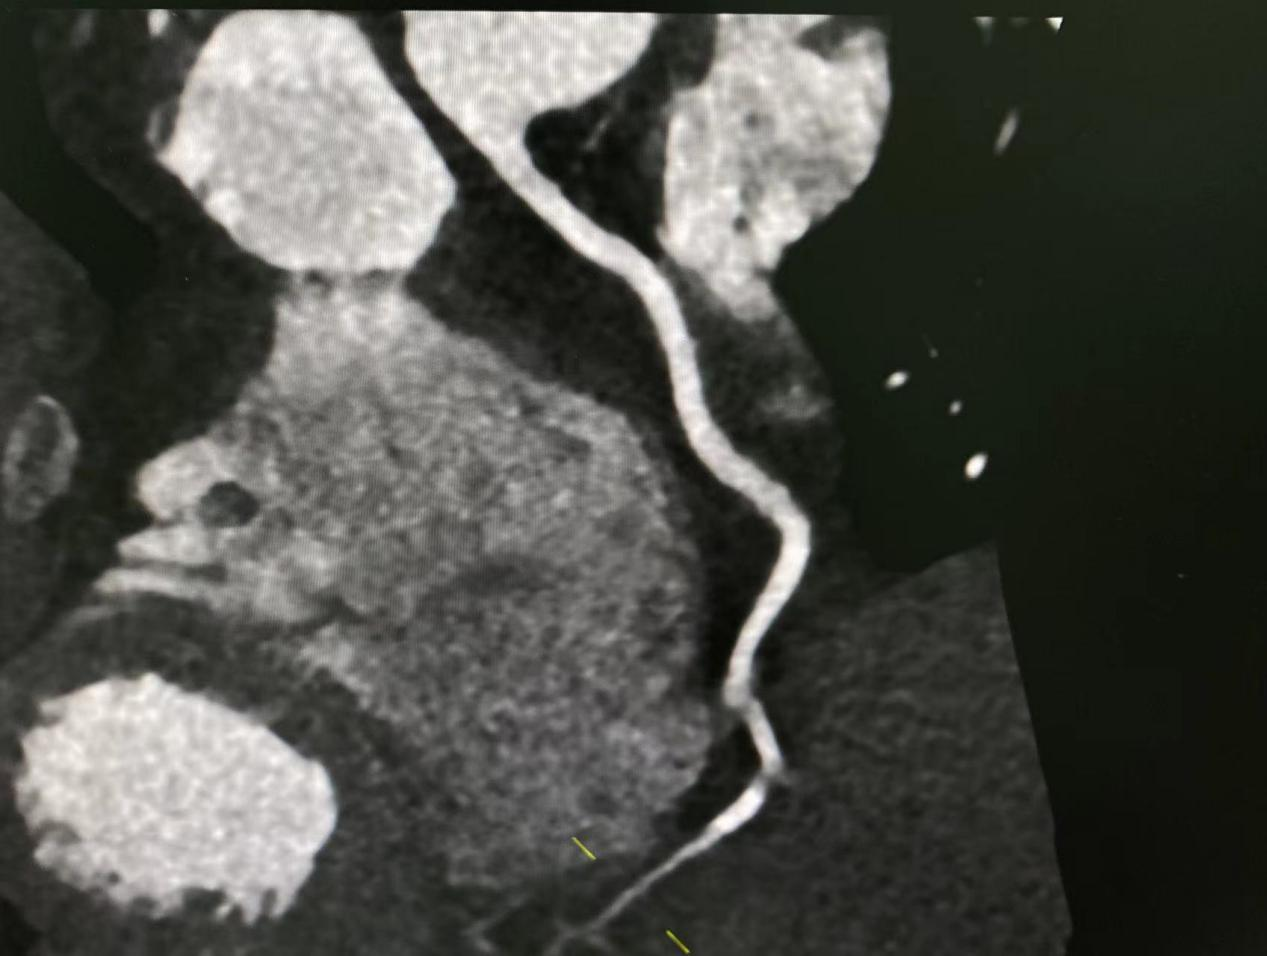

影像技师张锐准确的选择好扫描条件,计算好造影剂剂量、注射速率等方案后进行规范扫描,扫描完成,各支血管显示清晰,完成处理后传输到报告系统。

MIP

MPR

完成检查后,两位主任对图像、报告进行综合评价及审核。各项流程顺利,项目开展完好,填补我院血管强化检查领域空白,为我院医学影像发展开启了新的篇章!